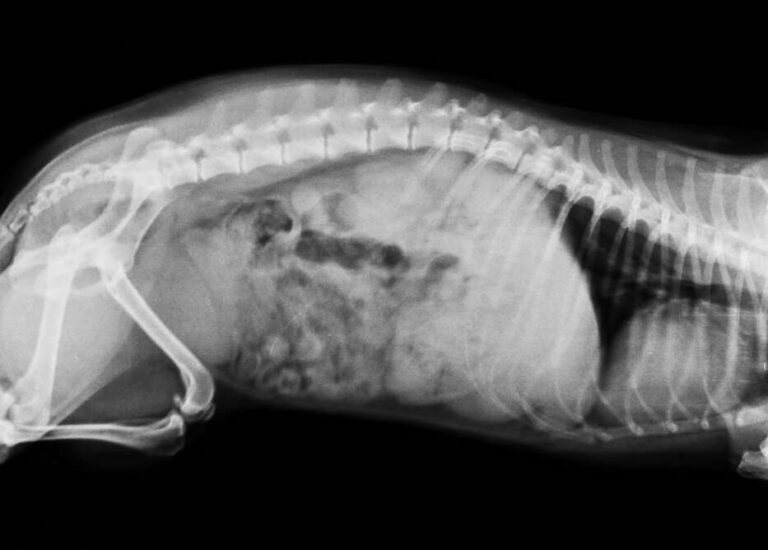

Anesthesia dental cleaning and polishing. You only need an X-ray if your doctor recommends it. This is a labeled normal feline DV dorsoventral chest X-Ray of a fat cat.

Cat x-rays are by far the most regularly used form of diagnostic imaging in the veterinary industry because they are cost effective comparatively speaking and they can accurately diagnose the state of skeletal structure and composition large body. This cat is laying on its right side. Depending on where your cat is injured the x-ray can cost anywhere from 100 to 250.

This is a normal cat lateral abdominal X-Ray. A surgical procedure if necessary can range anywhere from as little as 500 to as much as 3100 for the surgery by the time you add in. Leg X-rays can be used to determine the cause of pain in your legs detect abnormal growths and diagnose injuries.